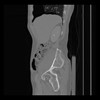

36 CUERPO,CE,Sagittal,3.000,CUERPO,Sagittal,